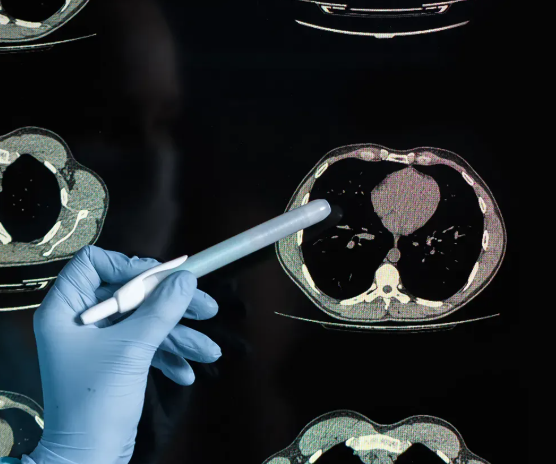

“흉부CT는 보이지 않던 몸속의 신호를 조용히 보여줍니다.”

정기 건강검진이나 가슴 통증으로 병원을 찾을 때, 의사가 “흉부CT를 촬영해보죠”라고 말하면 순간적으로 긴장하게 됩니다. 하지만 흉부CT는 단순히 병을 찾아내는 검사라기보다, 우리 몸이 보내는 미세한 변화를 세밀하게 기록하는 과정이라고 볼 수 있습니다. 특히 흉부ct로 볼수있는 질환은 생각보다 폭넓고, 단순 폐질환뿐 아니라 심장·혈관·종격동까지 포괄합니다.

CT는 ‘Computed Tomography’의 약자로, 인체의 단면을 수백 장 이상 촬영한 뒤 컴퓨터가 이를 합성하여 입체적인 이미지를 만들어냅니다. 엑스레이는 한 방향에서 찍은 단일 평면 이미지이기 때문에, 가슴 속 구조가 겹쳐 보이는 한계가 있습니다. 반면 CT는 다양한 각도에서 찍은 단층 이미지를 결합하므로, 기관이나 폐 속 병변의 위치와 크기를 훨씬 정확히 확인할 수 있습니다.

예를 들어 엑스레이에서는 갈비뼈 그림자에 가려진 작은 결절이 보이지 않더라도, CT에서는 뚜렷하게 구분됩니다. 이처럼 세밀한 관찰이 가능하기 때문에, 흉부ct로 볼수있는 질환은 폐렴이나 결핵 같은 감염성 질환을 넘어 종양, 혈관 이상, 심장 주위 구조의 이상까지 포함됩니다.